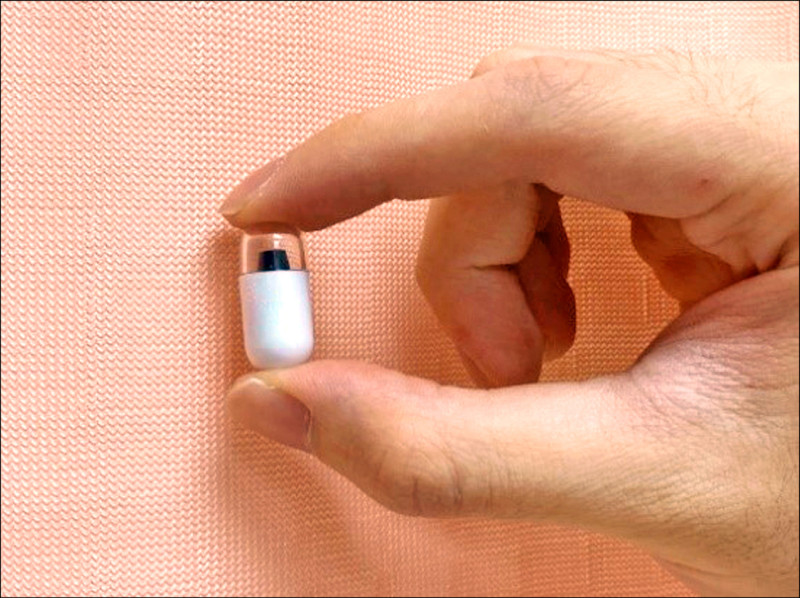

馬偕醫院內視鏡中心主任林煒晟形容,膠囊內視鏡大小如魚肝油膠囊,內藏微型攝影機,吞下後隨腸胃蠕動自然前進,全程自動拍攝消化道影像並回傳,不需麻醉也無須住院,檢查時間約8-15小時,24-48小時後隨排便排出,過程幾乎無感,自費費用約是6萬元。